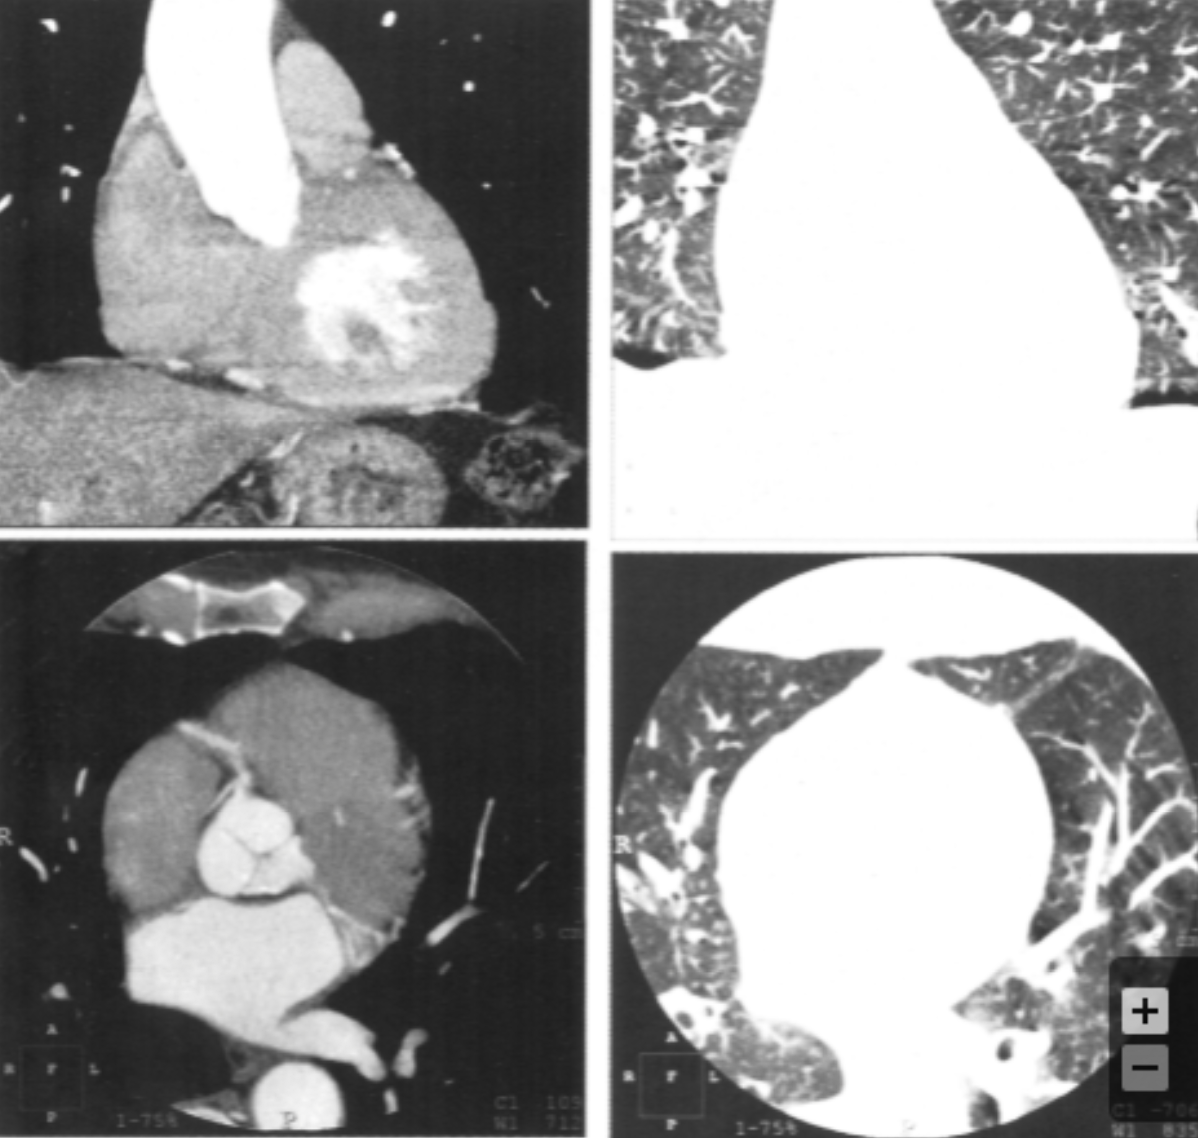

Describe the findings:

Beam Hardening Artifact

Describe the findings and diagnosis:

LV apical thrombus